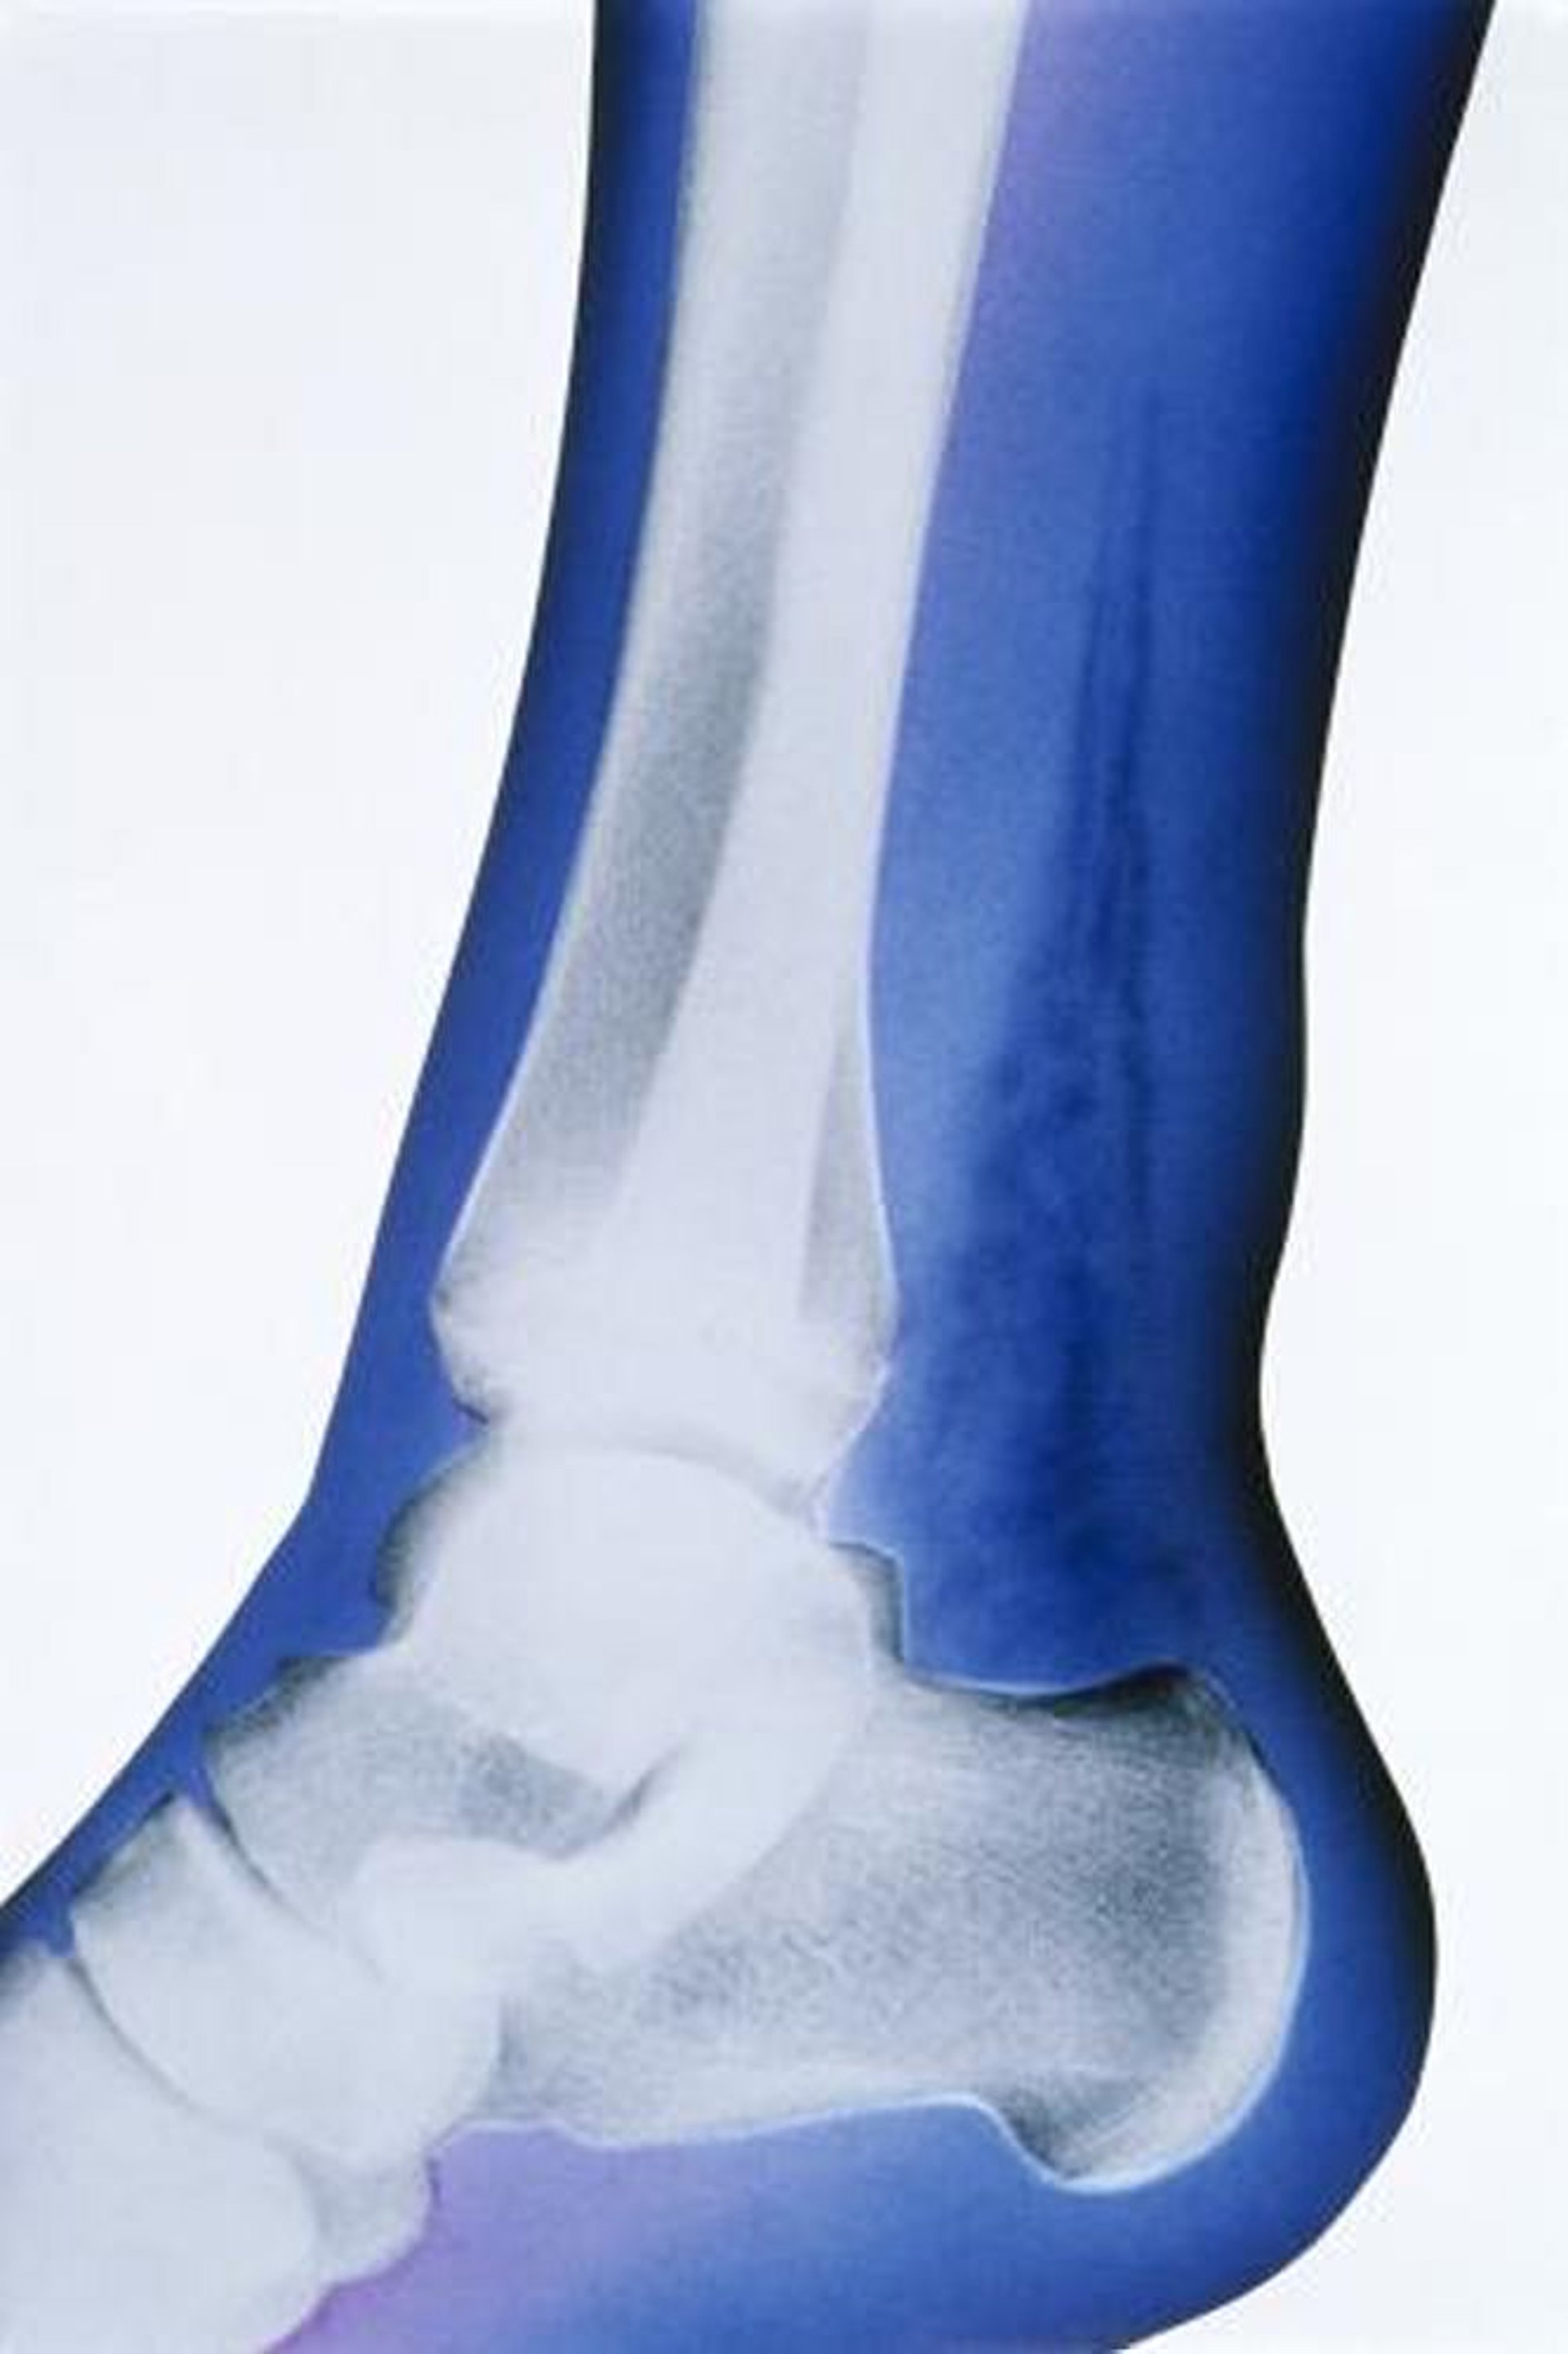

Infezione necrotizzante sottocutanea (RX)

In questa radiografia colorata artificialmente, il dato saliente è la presenza di gas nei tessuti molli, indicato dalle densità altamente radiotrasparenti sopra al calcagno e dietro alla tibia e al perone.